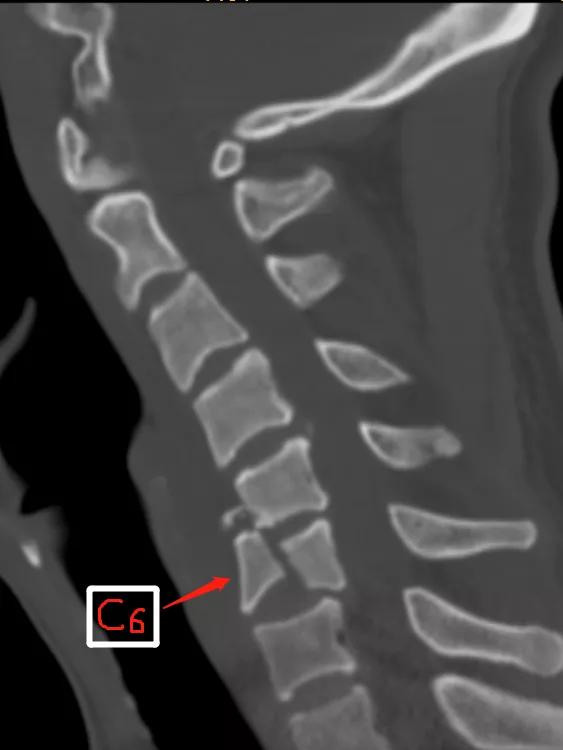

张先生是一名卡车司机,今年5月份发生了一场车祸,卡车侧翻,当时仅感觉右侧颈肩部酸痛和2个手指轻度麻木,便没有就医和检查。然而两个月后,却因为扁桃体周围脓肿来医院做CT,意外发现 颈椎骨折继发颈椎后凸畸形 。

此外,该患者颈6椎体前中柱骨折,后方结构尚稳定,如果行传统后入路,破坏附着的肌肉群,可能破坏原有的稳定性,同时术后可能存在颈部轴性痛的症状等。脊柱外科主任张昊与全科室医生进行充分讨论,查阅相关文献,与患者充分沟通病情和诊疗计划。与此同时,继续加强患者抗感染治疗,控制脓肿进一步恶化;给患者进行颅骨牵引,评估颈椎曲度改变情况,发现在颅骨牵引后患者颈椎骨折可部分复位,同时颈椎曲度也较前有恢复,最后决定为患者进行 “颈后路肌间隙入路颈椎骨折复位、后凸畸形矫正、钉棒系统内固定、植骨融合术”。该技术具有手术创伤小,术中保留了绝大部分肌群、出血较少,术后患者无明显颈部轴性疼痛的症状等优点,最后患者满意出院。